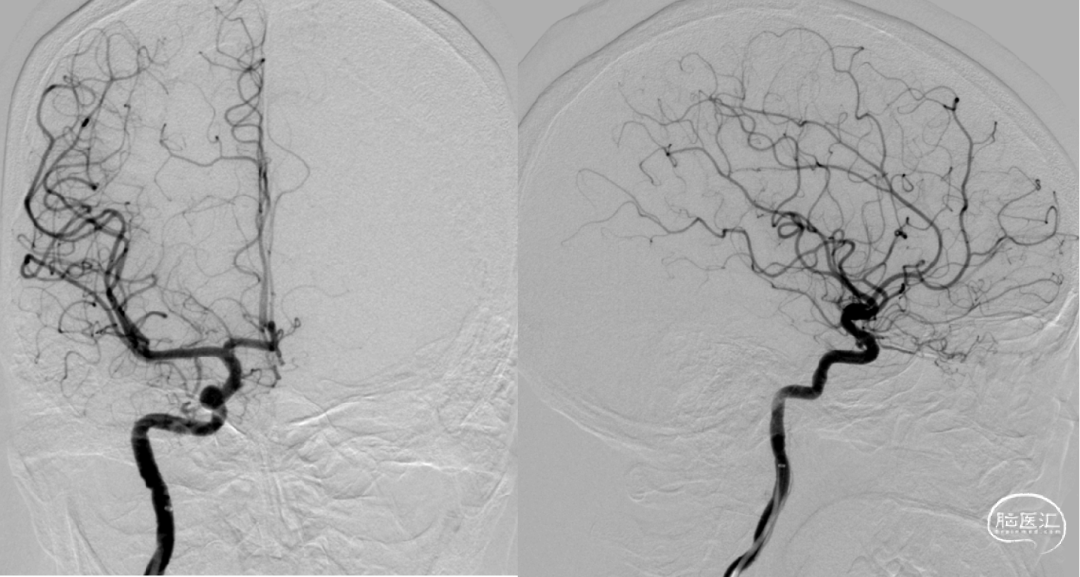

术后即刻造影